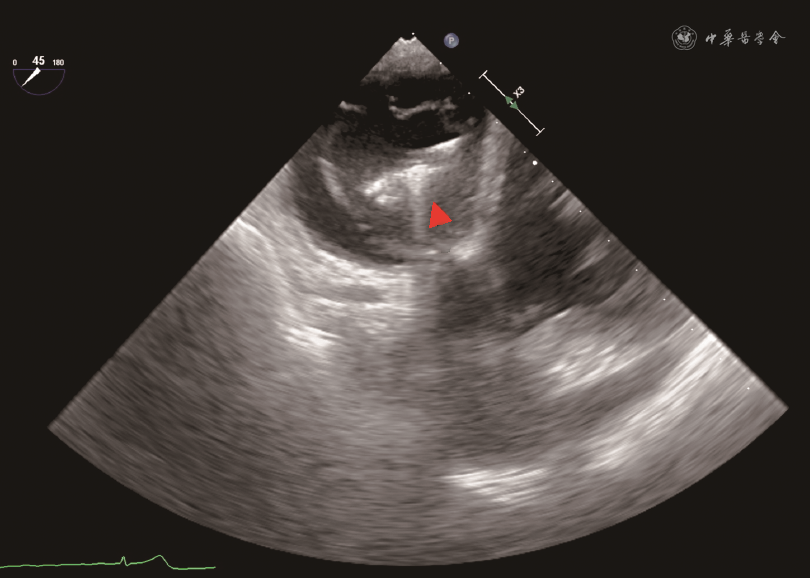

经导管三尖瓣缘对缘修复手术在全身麻醉、气管插管下进行。本研究所使用的经导管三尖瓣缘对缘修复器械为淇麟三尖瓣缘对缘修复系统(上海申淇医疗科技有限公司)、Neoblazar经导管三尖瓣夹合器及输送系统(江苏臻亿医疗科技有限公司)。本文所描述的手术过程以淇麟三尖瓣缘对缘修复系统为例。经右侧股静脉穿刺送入加硬导丝,在TEE 双腔切面引导下将导丝送入上腔静脉。使用18 Fr(1 Fr=0.33 mm)扩张子扩张股静脉穿刺处。将导引鞘头端调直,在TEE Bicaval View引导下沿导丝送入导引鞘使其头端位于右心房中部。若导引鞘头端朝向房间隔,可通过向L方向旋转S/L旋钮,或调整导引鞘+/-旋钮增加头端弯度并逆时针旋转导引鞘,使导引鞘头端远离房间隔(图1)。在体外预先测量导引鞘和夹子输送系统的位置关系,并在夹子输送系统上做标记。将夹子输送系统从导引鞘中送入右心房,在TEE双腔切面引导下送入标记深度,完成导引鞘和输送系统的对位,使夹子头端位于右心房中部。TEE显示右心室流入道/流出道切面及Biplane切面(图2),向F方向旋转夹子输送系统上F/E旋钮,使夹子朝向三尖瓣(图3)。通过旋转导引鞘、调整导引鞘S/L旋钮和输送系统F/E旋钮,使输送系统头端运动轨迹在上述两个TEE切面上都和三尖瓣水平垂直。若夹子输送系统从间隔斜向三尖瓣时,被称为“间隔拥抱”(Septal Hugger)现象(图4),可通过向L方向旋转S/L旋钮并顺时针旋转导引鞘调整。通过向患者头端推送或向脚端回撤整体系统,使夹子输送系统在TEE右心室流入道/流出道切面朝向反流束。打开夹子到120°,旋转夹子输送系统手柄使夹子在TEE经胃底短轴切面垂直于反流处瓣膜对合缘(图5)。关闭夹子,操作夹子输送系统手柄,将夹子送入右心室三尖瓣瓣下,切勿送入过深。打开夹子到120°,再次在TEE经胃底短轴切面确定夹子方向。顺时针旋转或逆时针旋转导引鞘,将使夹子分别靠近三尖瓣隔瓣或前(后)瓣,同时回撤夹子输送系统手柄,用夹子捕获三尖瓣隔瓣或前(后)瓣。通常使用TEE右心室流入道/流出道切面及Biplane切面来显示和引导捕获瓣叶,若此切面图像不能清晰显示夹子是否成功捕获瓣叶,可以通过TEE经胃底短轴切面显示瓣叶活动被夹子限制来判断夹子是否捕获瓣叶(图6)。确定夹子捕获瓣叶后,放下上夹壁(Gripper),缓慢关闭夹子,关闭夹子过程中可通过TEE经胃底短轴切面观察到瓣叶活动受限并随着夹子关闭隔瓣或前(后)瓣聚拢(视频1,TEE显示夹子关闭过程,请扫描文章首页二维码观看)。关闭夹子后,TEE检测三尖瓣反流情况,夹子夹持瓣叶长度,评估是否需要调整夹子位置或因夹持瓣叶长度不足而进行再次夹持,以及是否需要补充额外的夹子。评估满意后按照夹子释放流程释放夹子。

因三尖瓣位于心脏的前方,距离食管较远,且容易受到左心人工瓣膜以及夹子输送系统的声影影响,经食管超声探头位于食管中下段时,有可能不能提供足够清晰的图像显示夹子捕获三尖瓣。将食管超声探头送到胃部,并将食管探头前屈并向患者右侧旋转,在20°~60°范围内调整产生的经胃底短轴切面,避免了左心或输送系统的声影影响,可在一个二维平面同时显示三尖瓣三个瓣叶的结构,在此切面使用Biplane功能,可获得显示三尖瓣前瓣和后瓣的右心室长轴图像,可以辅助判断夹子进入右心室的深度,但不能为夹子捕获瓣叶提供引导。利用经胃底短轴图像进行三维图像重建,再利用Multiview进行图像分割重建,可精准获得和夹子重合的超声切面,显示夹子和瓣叶的关系,可用于引导瓣叶捕获和判断捕获程度(图6)。但因进行Multiview图像重建后,图像清晰度会有明显下降,因此对于重建前的二维超声图像有较高的质量要求。因此,经胃底短轴切面在经导管三尖瓣缘对缘修复手术中诸如夹子位置和方向的调整、瓣叶捕获判断、瓣叶夹持程度的判断等重要步骤中发挥关键作用[20]。如右心严重扩大或存在心脏转位,食管中段切面和经胃底短轴切面均无法提供满足引导要求的图像时,可使用心腔内超声[21]。